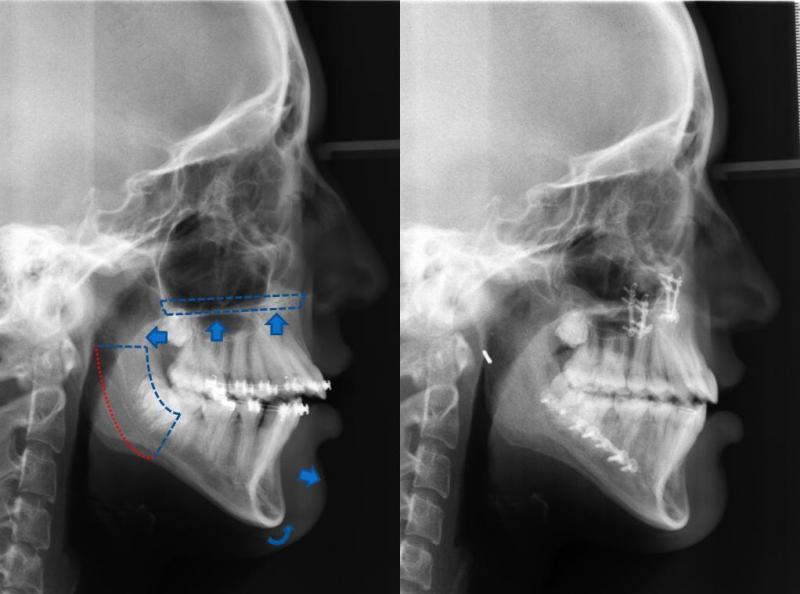

Diagnosis and treatment of dysgnathia, and orthognathic reconstructive surgery, genioplasty, maxillo-mandibular advancement/set-back, and surgical correction of facial asymmetry (See Images Below)

Orthognathic Surgery (Class II)

Orthognathic Surgery (Class III)

Orthognathic Surgery (Class II with 'Gummy Smile')